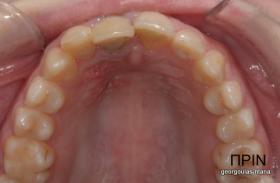

ΑΠΟΚΑΤΑΣΤΑΣΗ ΑΝΩ ΚΕΝΤΡΙΚΟΥ ΤΟΜΕΑ ΜΕ ΜΟΝΗΡΕΣ ΕΜΦΥΤΕΥΜΑ

Η κοπέλα αυτή ήρθε στο ιατρείο με κάταγμα στον δεξιό άνω κεντρικό τομέα. Το δόντι είχε απονευρωθεί στο παρελθόν και είχε αποκατασταθεί με βιδωτό άξονα κ ανασύσταση με ρητίνη και το αισθητικό αποτέλεσμα ήταν φτωχό. Η ασθενής ήθελε να είναι καλυμμένη αισθητικά για όσο χρονικό διάστημα θα διαρκούσε η θεραπεία. Πραγματοποιήθηκε τομογραφία κωνικής δέσμης (CBCT) στην περιοχή και αποφασίστηκε να γίνει εξαγωγή του δοντιού, διατήρηση του όγκου του φατνίου και 3 μήνες μετά τοποθέτηση εμφυτεύματος με ταυτόχρονη χρήση μοσχευμάτων σκληρών κ μαλακών ιστών  για βέλτιστο αισθητικό αποτέλεσμα. Το εμφύτευμα αποκαταστάθηκε με υβριδικό κολόβωμα από διπυριτικό λίθιο και ολοκεραμική στεφάνη από διπυριτικό λίθιο (Emax). Καθ’ όλη τη διάρκεια της θεραπείας, η ασθενής ήταν καλυμμένη αισθητικά με γέφυρα Meryland  συγκολλημένη στα δύο διπλανά δόντια. Μετά την οστεοενσώματωση του εμφυτεύματος και πριν την τελική αποκατάσταση, τοποθετήθηκε στο εμφύτευμα προσωρινή εργασία με σκοπό τη βελτίωση των ούλων.